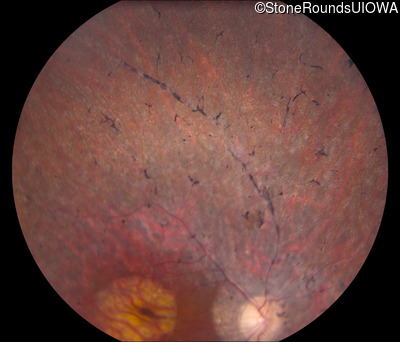

Fundus Photography - Left - 20/32

Exemplar